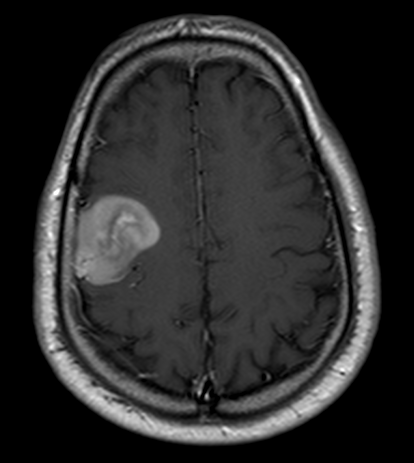

Resezione microchirurgica di tumore cerebrale (glioma alto grado cortico-sottocorticale) frontale dx